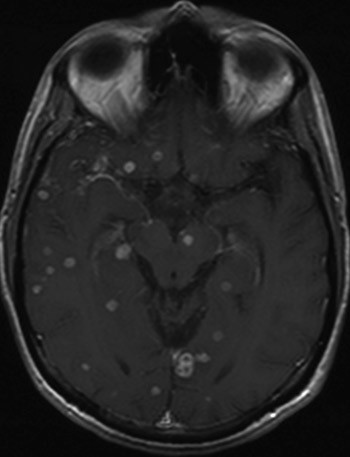

Pasienten var fortsatt kvalm og kastet opp, men konsentrasjonen av rifampicin i serum tydet på godt tarmopptak og tilstrekkelig dosering. Etter tre uker med medikamentell behandling var det symptomforverring. Det ble da startet opp med intramuskulære injeksjoner med amicacin (Biklin) som tilleggsmedikament til de perorale medikamentene. Etter dette var det rask bedring. MR caput ble deretter utført og viste utallige tuberkulomer i både lillehjernen, storhjernen og hjernestammen, med ødemer omkring (fig 3). I tillegg fant man fortykkede meninger over høyre hemisfære av storhjernen. På ny ble steroidbehandling vurdert, uten at dette ble gitt.

Til sammen fikk pasienten antituberkuløs behandling i 12 måneder. Ved siste kontroll tre år etter innleggelsen var han i god allmenntilstand og i fullt arbeid. MR caput tatt ca. ett år etter avsluttet behandling viste betydelig tilbakegang av tuberkulomene (fig 4).